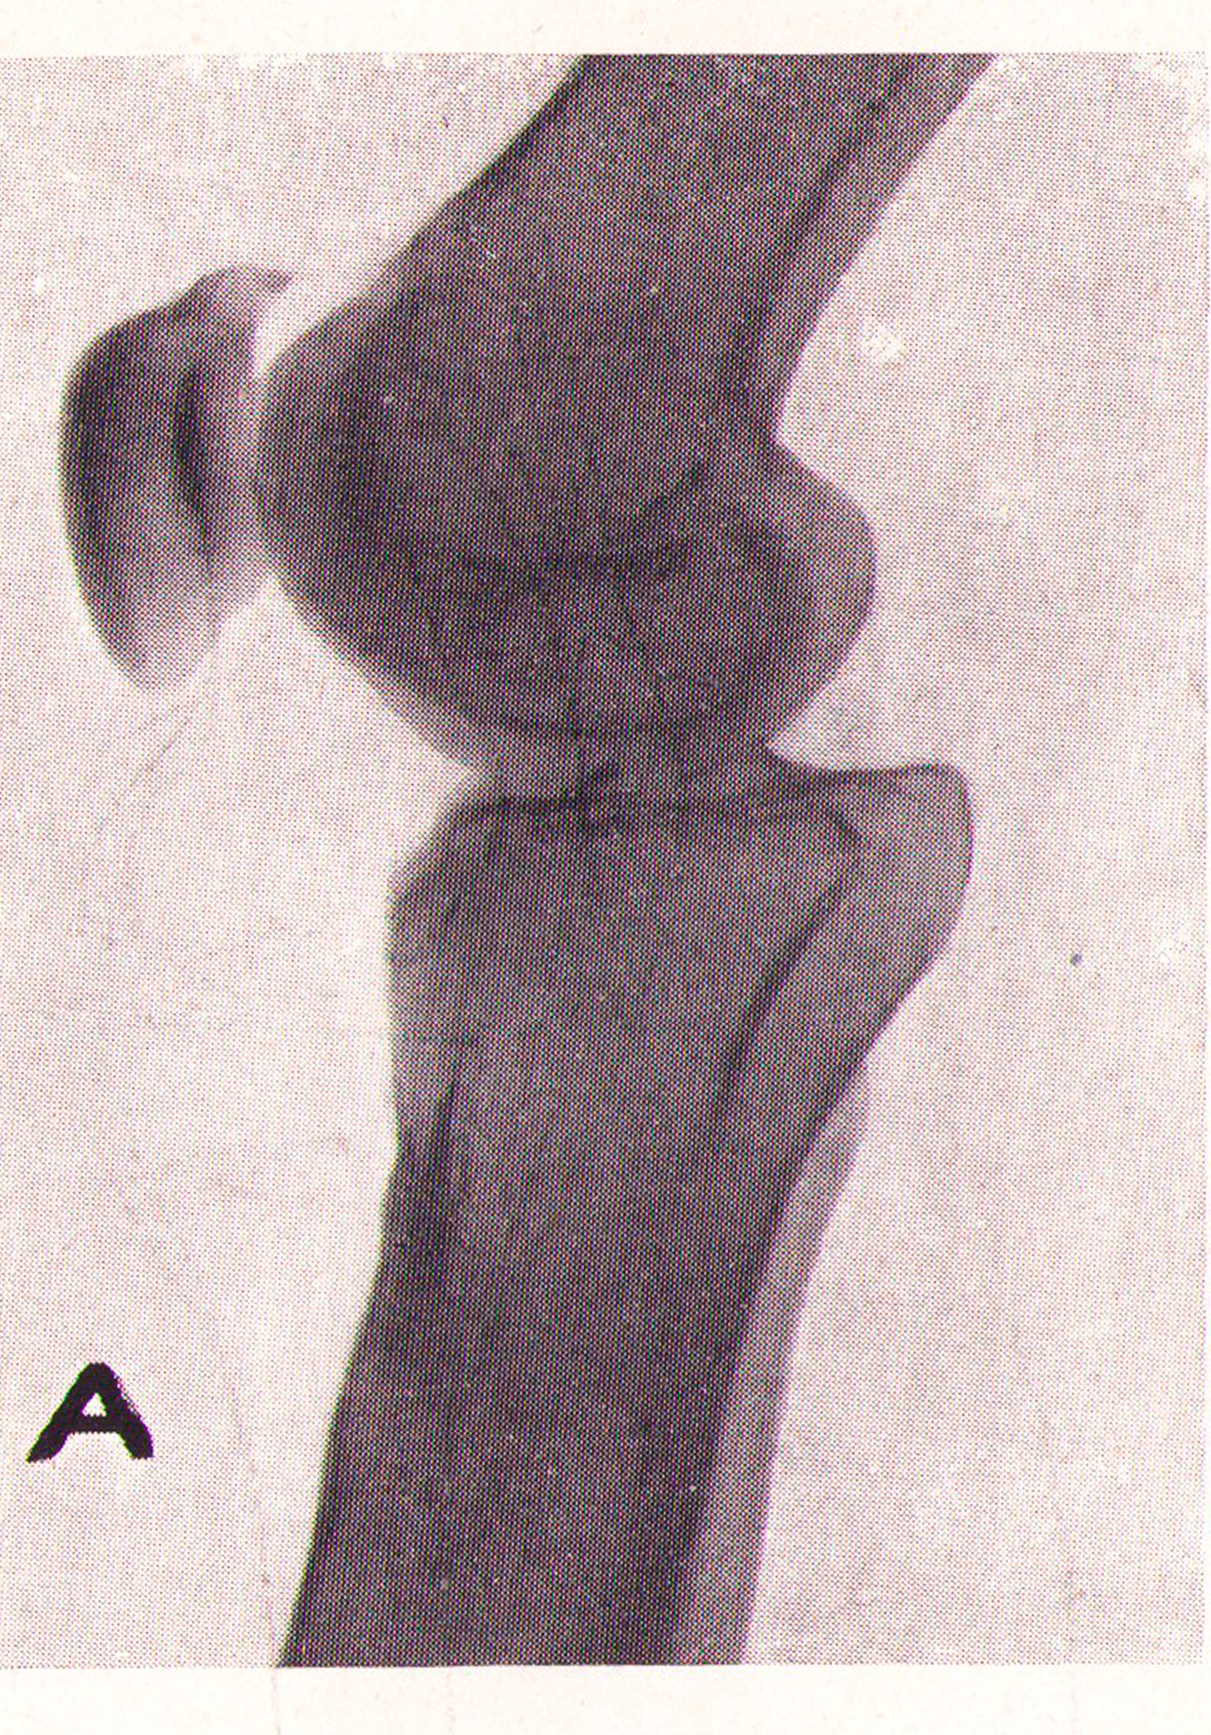

Radiografía antero-posterior de la hendidura articular desaparecida

Revista Española de ciencias médicas, Clínica y laboratorio, Tomo XXXV, 1943.